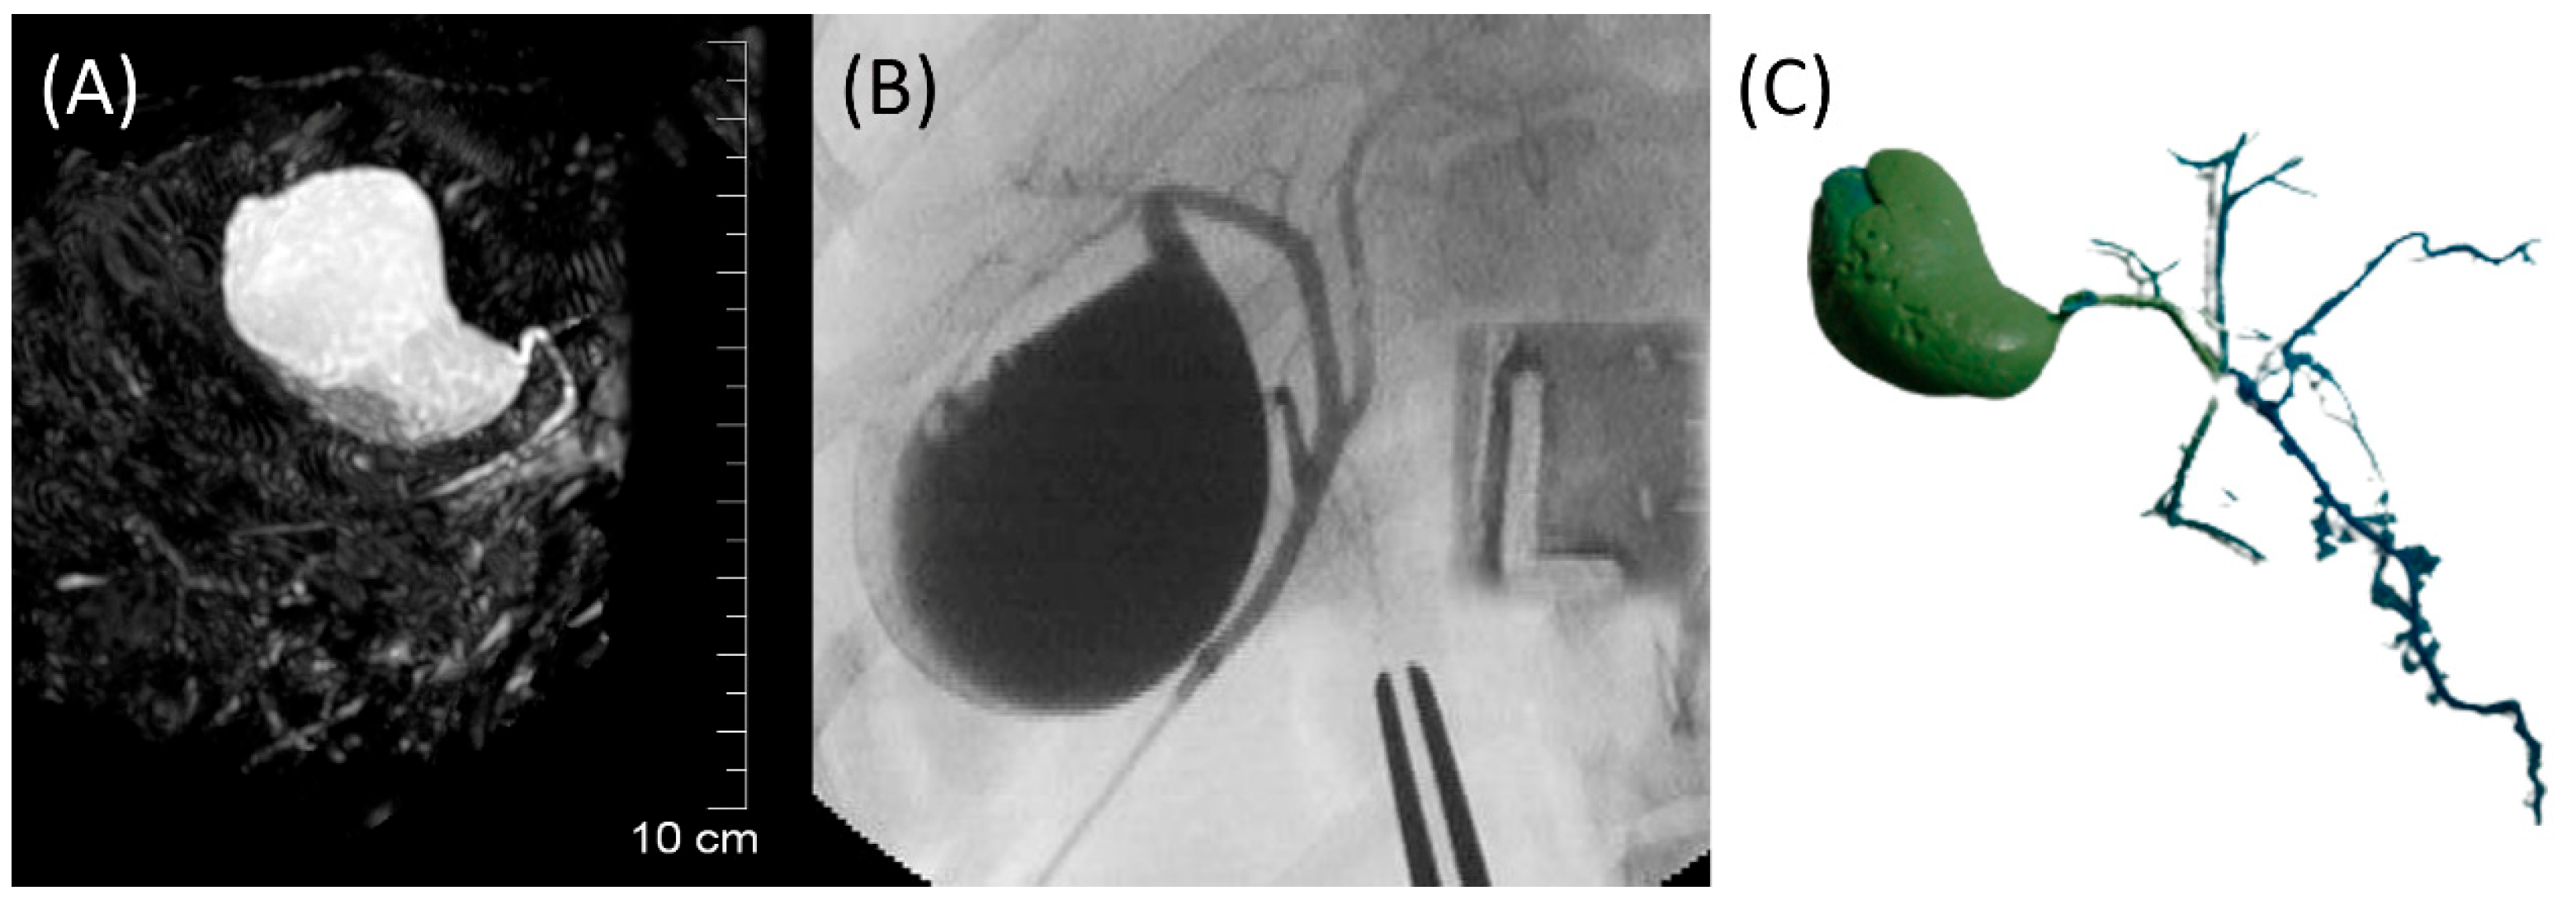

The GB (fundus, body, and neck), cystic duct, and CBD (at papilla and at extrahepatic ducts’ junction) were visible in MRCP, FRCP, and corrosion casting in all eight dogs. Visual comparisons between MRCP, FRCP and corrosion casting in Dog 6 with no evidence of disorders and Dog 8 with biliary disorders are shown in Figure 2 and Figure 3, respectively. The extrahepatic ducts and pancreatic ducts were variably visible in the MRCP and FRCP images. This did not allow for statistical analysis, only descriptive assessment.

Figure 2. Images of Dog 6 with no evidence of biliary and pancreatic disorders. (A) 3D-TSE-MRCP image showing normal gallbladder, cystic duct, and common bile duct. (B) FRCP image demonstrating normal biliary tract filled with contrast material. (C) Corrosion cast demonstrating normal biliary tract.

Figure 3. Images of Dog 8 with acute extrahepatic cholestasis and focal destructive cholangitis. (A) 3D-TSE-MRCP illustrating dilated gallbladder neck (arrowhead). Normal left extrahepatic duct is visible (arrow). (B) FRCP image showing dilated gallbladder neck (arrowhead). (C) Corrosion cast demonstrating dilated gallbladder neck (arrowhead).